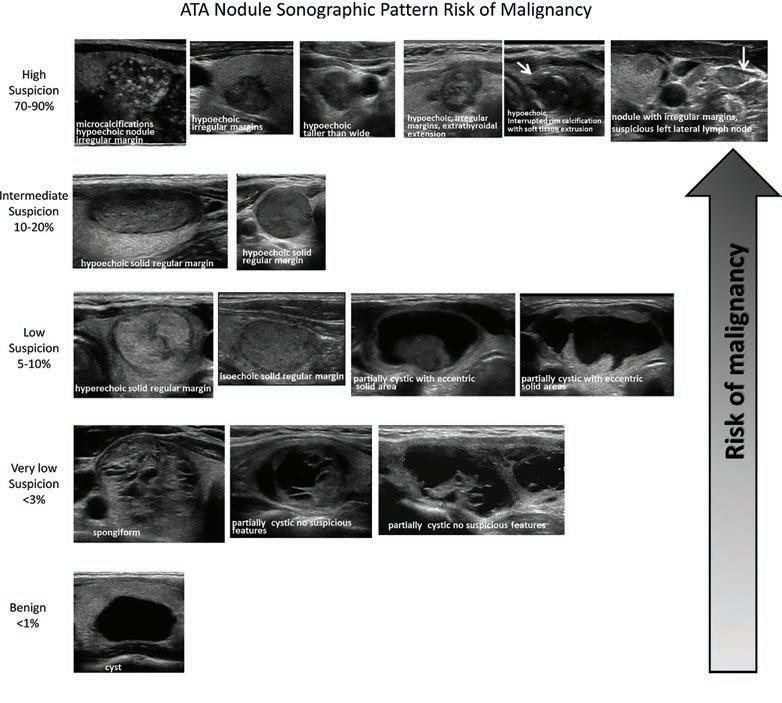

47 Thyroid Nodules – the good, bad and ugly A/Prof Ming Khoon